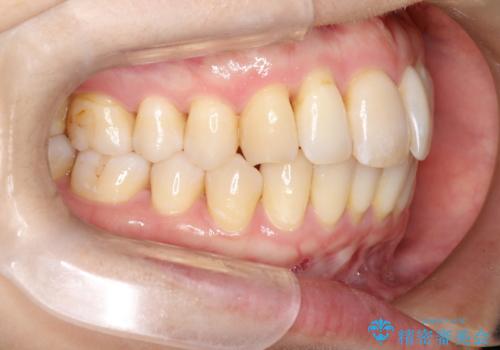

以前ワイヤー矯正をされていた方は、装置をつけての再矯正を希望されない方もいます。

その場合にインビザラインをお勧めさせていただいております。

後戻りがわずかな場合は、期間も短くて済む場合があります。